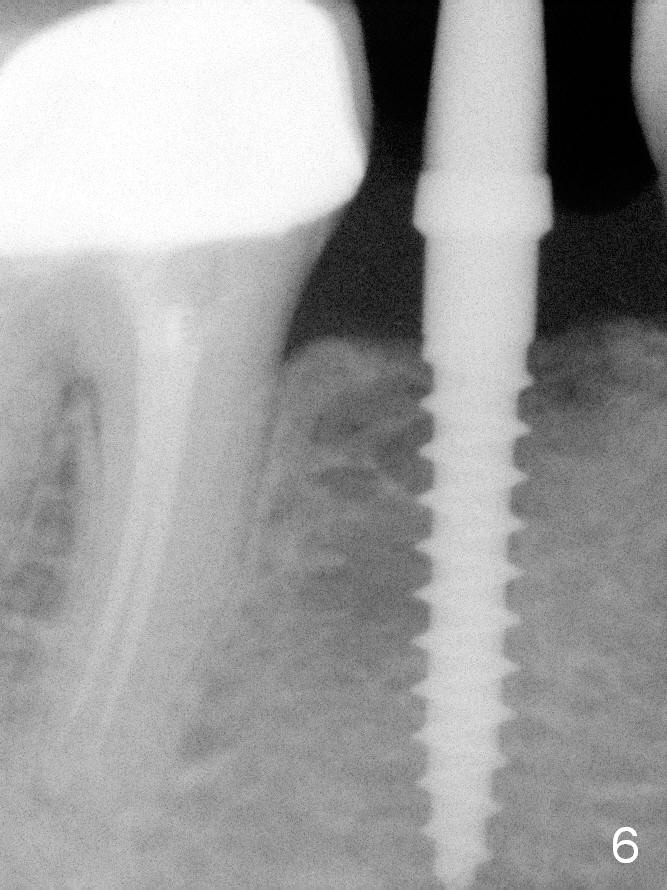

A 2.5x12(2) mm 1-piece implant is placed (Fig.6). There is mild bone loss distal 4 months postop (Fig.8 * (possible artifact due to angulation)).